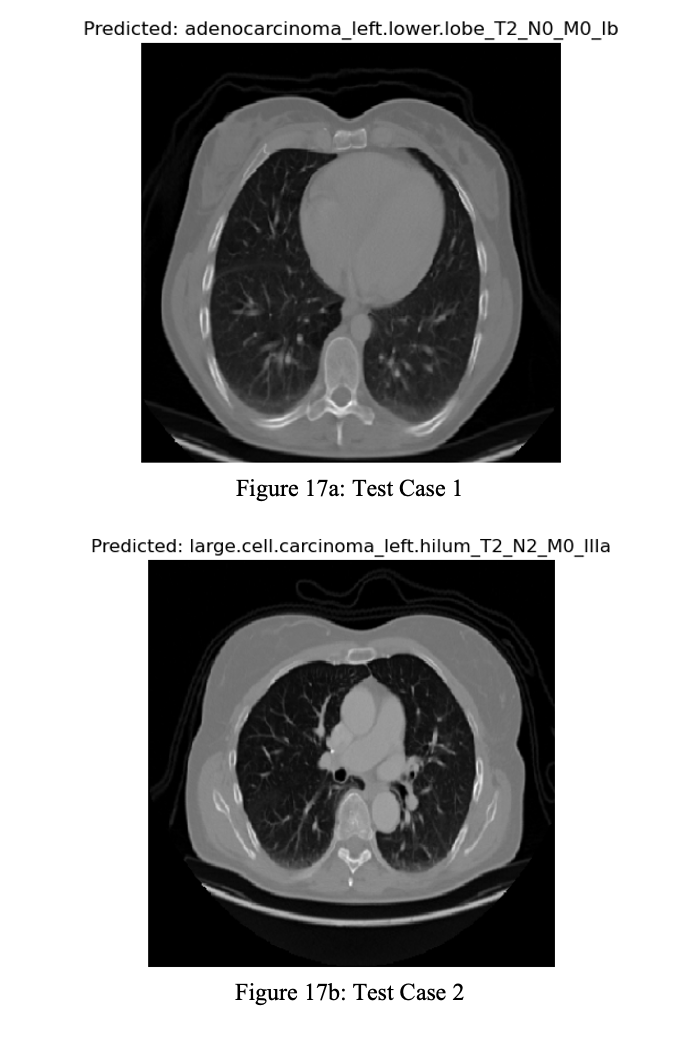

The model was used to make predictions on the Chest CT Scans dataset and the IQ-OTH/NCCD dataset. In (Figure 17a to Figure 17d), the model takes different samples belonging to each class of the Chest CT Scans dataset and predicts which class the Chest CT scan image belongs to.